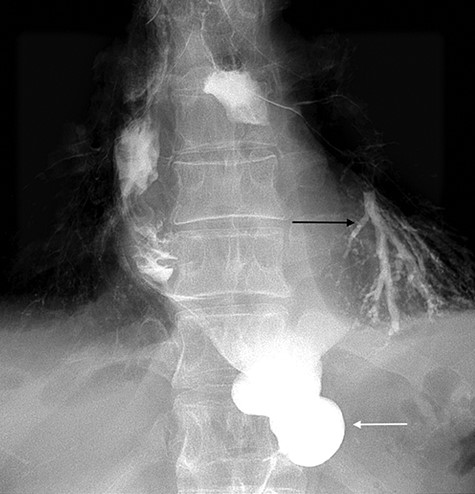

After this endoscopic procedure, the patient was subjected to barium swallow examination that demonstrated the OTSC on the gastric conduit and no filling of the left bronchus (Figure 3), following by complete resolution of symptoms. At the follow-up time of 6 months, the patient is asymptomatic and there is no recurrence of the fistula. To the best of our knowledge, this is the first reported case of GBF treated with OTSC in the literature.

Postoperative barium swallow demonstrating the OTSC on the gastric conduit (white arrow) and no filling of the left bronchus.